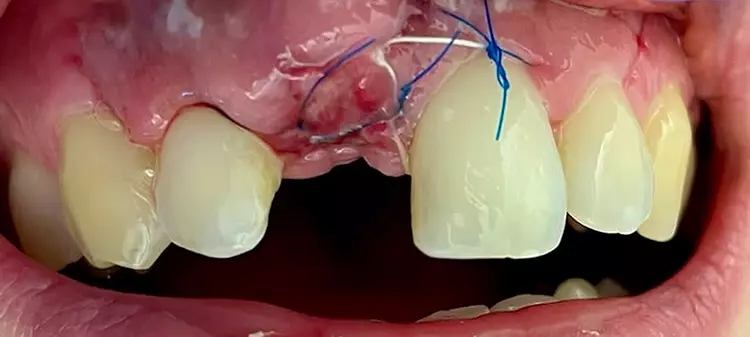

In einem zweizeitigen Vorgehen wurde der Defekt im Sonic Weld Rx-Verfahren mittels Eigenknochen und BioOss (Geistlich, Wolhusen, Schweiz) im Verhältnis 1:3 augmentiert. Der autologe Knochen wurde über der Defektregion paranasal mittels Trepan gewonnen und mit BioOss gemischt. Um die ursprüngliche Kontur des Alveolarfortsatzes mit dem charakteristischen Jugum alveolare wiederherzustellen, kam der entsprechend vorgeformte Alveolenprotektor zur Anwendung.

Zahnklinik Bochum

Die Nähte wurden 10 Tage post operationem entfernt. Um das Schwellungs- und Entzündungsrisiko zu minimieren, wurden der Patientin ein Antibiotikum und Analgetikum rezeptiert sowie auf intensives Kühlen hingewiesen.